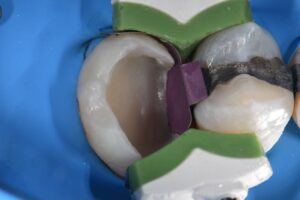

Extreme DME case using the Rhondium DME wedge in sequence with the Garrison Compositight system with a supercomposite placed incrementally to support what little is left of this extremely-compromised second bicuspid.

#VocoGrandioSO #RhondiumDME #GarrisonCompositight